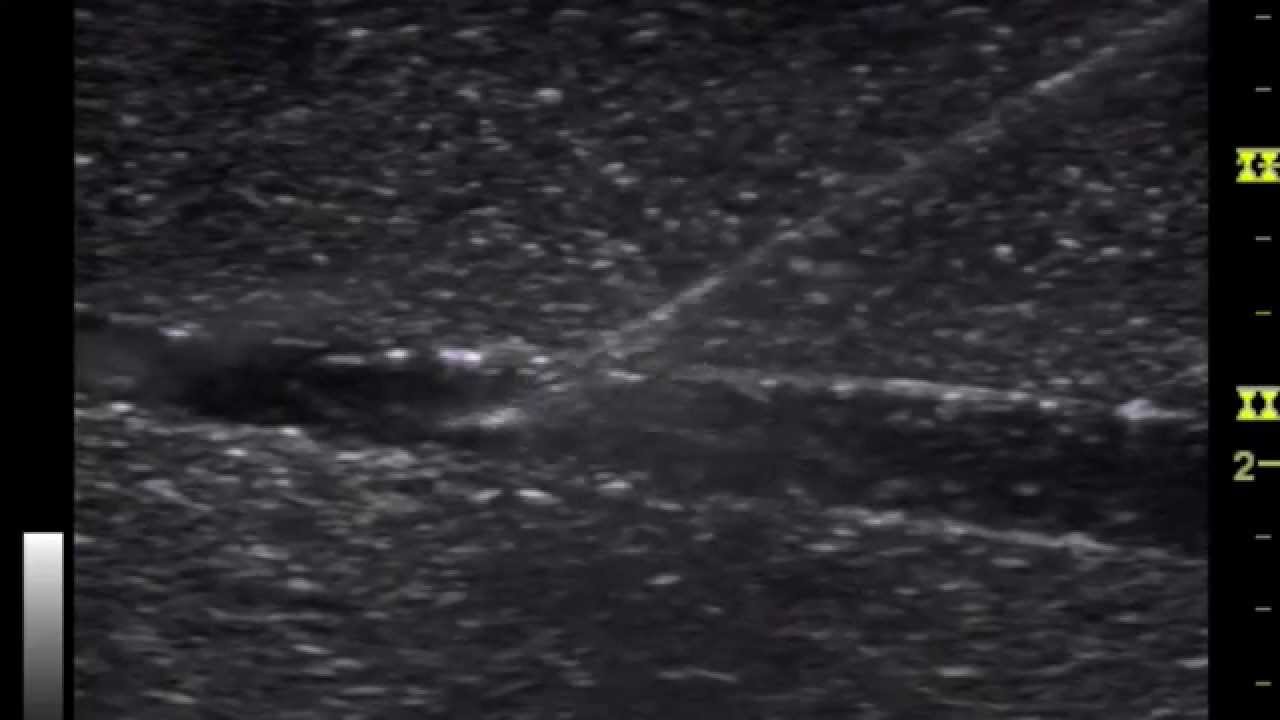

Instructional Series Sonon Needle Visualization YouTube Needle Guide Ultrasound Civco ultrasound needle guides help improve needle visualization, reduces procedure time, and provides confident clinical outcomes during. Radiology, anesthesia, pain management, and vascular access. These procedure needle guides are intended for alignment and synchronization of the needle with the ultrasound transducer probe position and essentially keep the needle path under the ultrasound beam. Ultrasound needle guides are indicated for the. Needle Guide Ultrasound.